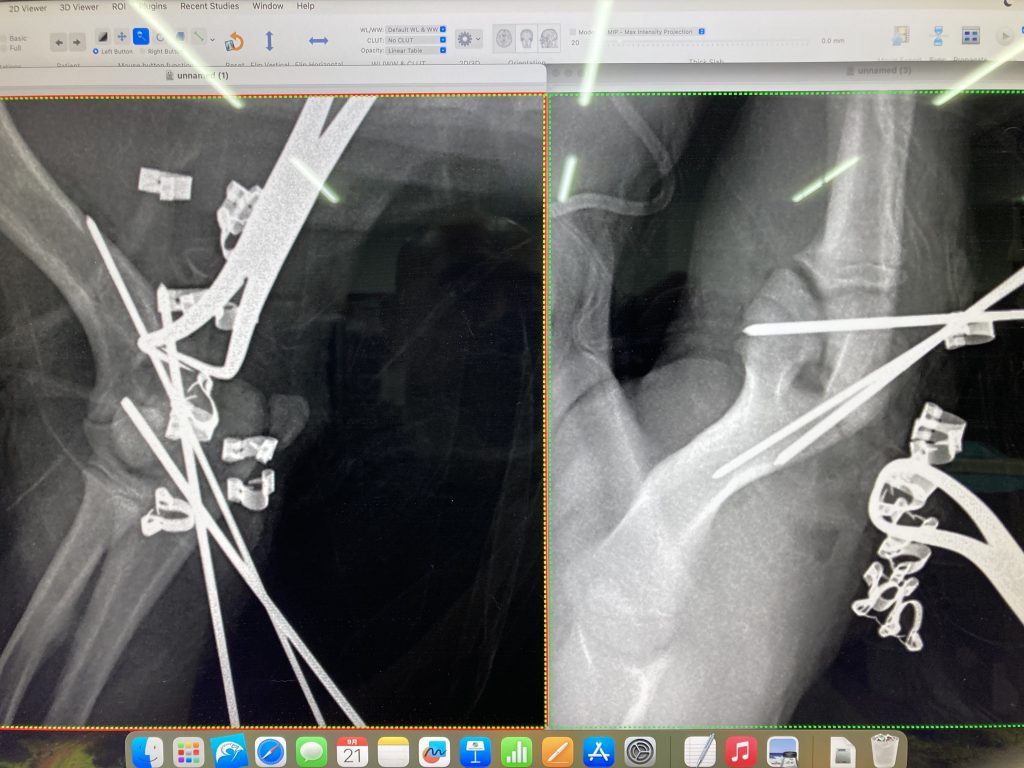

あの指はオーナーの決断によって手術となりました

腫瘍を疑い手術ですので、術前にCT検査です

暫定診断:爪の腫瘍

レントゲン検査では爪の骨が溶解していました

高齢ですが手術をお勧めしました

決断はオーナーにゆだねられます